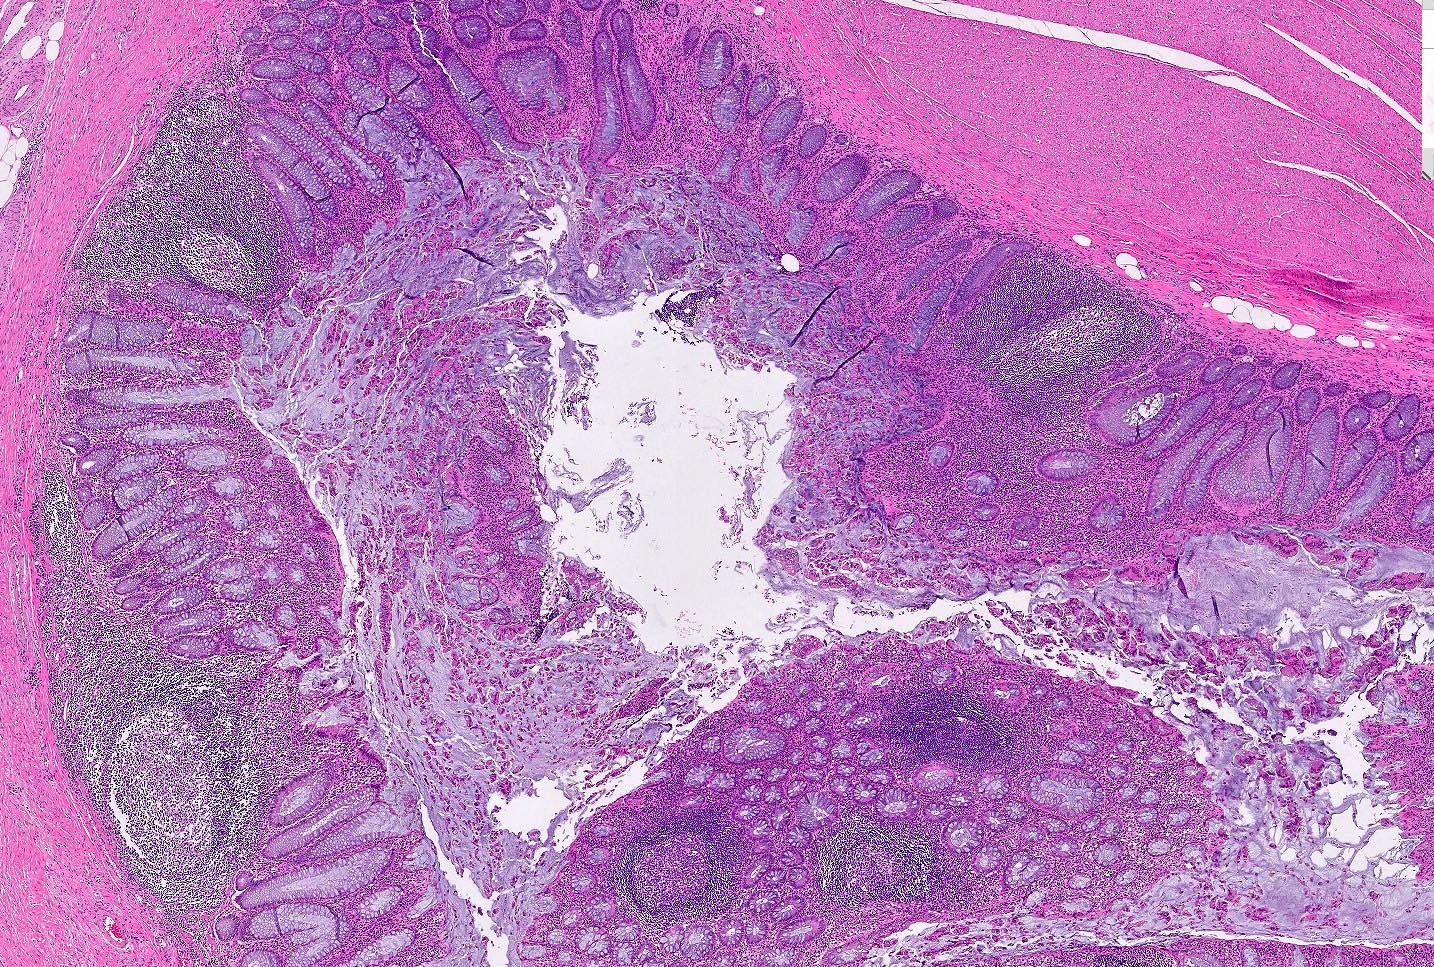

Microscopic (histologic) description

- Mucosa may be normal to markedly abnormal

- Expansion of lamina propria by lymphoplasmacytic infiltrate (more prominent in basal half)

- Lymphoglandular complexes, mucin depletion, focal Paneth cell metaplasia (in chronic cases) may be seen (J Clin Gastroenterol 2004;38:S11)

- Muscularis mucosa extends towards surface between elongated crypts

- Shortening of the affected bowel and hypertrophy of circular muscle layer (myochosis) leads to exaggerated mucosal folds (Am J Surg Pathol 1991;15:871)

- Some cases can show lamina propria fibrosis, crypt elongation on the tips of prominent mucosal folds, like mucosal prolapse syndrome in rectum and anus (J Clin Gastroenterol 2008;42:1137)

- Hemosiderin deposition in submucosa may be seen (StatPearls: Diverticulosis [Accessed 21 April 2022])

- Can mimic inflammatory bowel disease

- Hyperplasia of lymphoid aggregates is one of the earliest signs of diverticulitis

- Cryptitis, crypt abscesses, peridiverticular abscess and fistulas may be superimposed on this background in acute diverticulitis

- Tracking abscesses can spread longitudinally or circumferentially and can cause diverticular colitis

- Persistent localized inflammation can lead to phlegmon which is a thickened, firm segment of bowel wall that can lead to strictures and acute or subacute large bowel obstruction (Best Pract Res Clin Gastroenterol 2002;16:543)

Microscopic (histologic) images

Contributed by Bindu Challa, M.D. and Martha M. Yearsley, M.D.